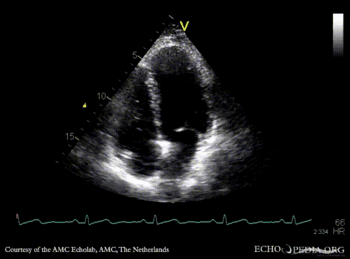

Contrast echocardiogram

AMC Echolab, AMC, The Netherlands

A4CH: jump rope IAS